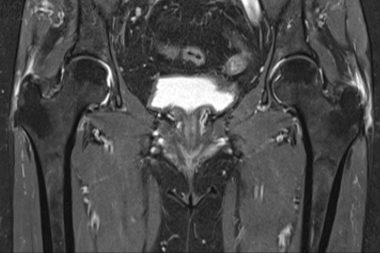

Trocanteritis; la causa de dolor de cadera que pasa desapercibida y cómo tratarla de forma definitiva